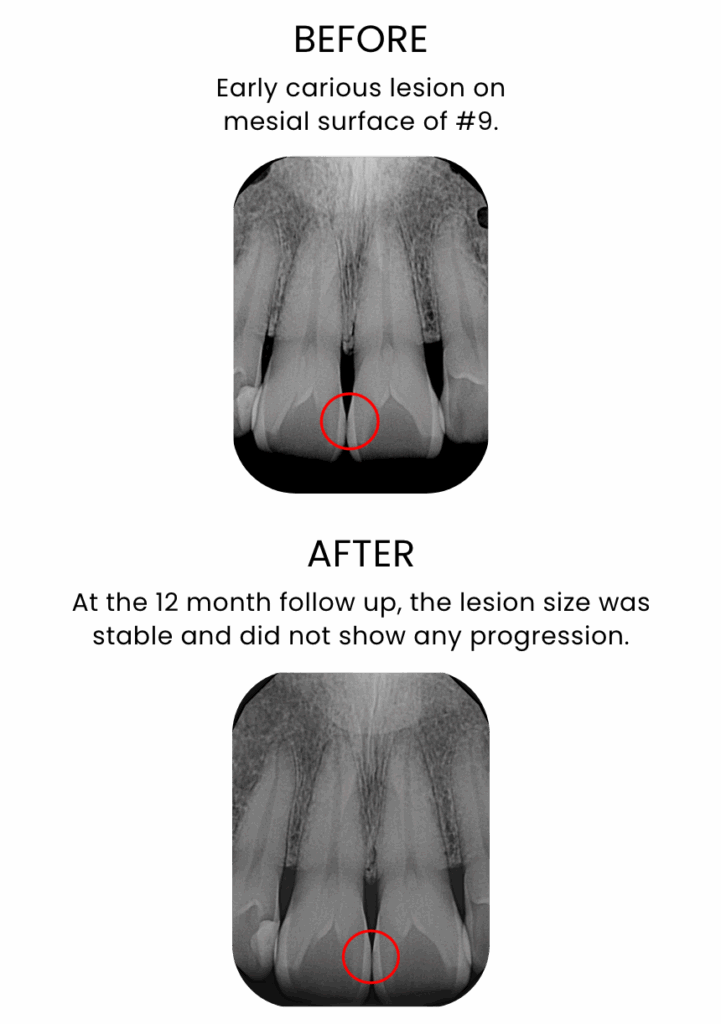

Interproximal early carious lesion in the aesthetic zone

50-year-old male patient

Courtesy: Dr. Gavin Miller

Scientific and real-world evidence has demonstrated that one application of Curodont Repair Fluoride Plus is sufficient to treat one lesion, with a success rate of over 90%. (Shaalan O et al. Clin Oral Investig. 2024;28:438)

Success with Curodont Repair Fluoride Plus is seen as the stopping of the progression of the treated lesion and the restoration of mineral density throughout the depth of the lesion, with studies showing a success rate of over 90%.(Shaalan O et al. Clin Oral Investig. 2024;28:438)

A recent study demonstrated that Curodont Repair Fluoride Plus led to a significant increase in mineral density throughout the lesion depth within only 2 weeks using Micro-CT and Scanning Electron Microscope analysis. [Cowen M et al. Biomater Res Rep 2025 Aug;175 Curodont™ Repair Fluoride Plus – Dental Advisor (Accessed 04/28/2026)]

Due to the limitations of currently available diagnostic technologies in clinics, such as x-rays, the improved mineral density may not be immediately visible on x-rays.